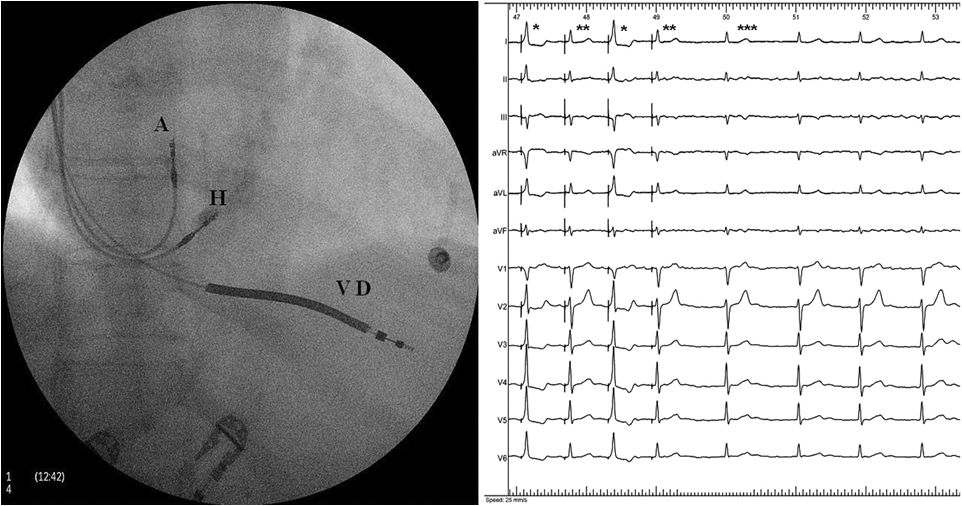

希氏束起搏图像

首次提出把希浦系统起搏纳入CRT再同步治疗方法

希氏束起搏与传统CRT对比研究

多中心,回顾性研究

PatientGroup I:CRT植入失败或无反应

PatientGroup II:符合CRT适应证但直接行HBP的患者

临床结果

植入成功率90%

对于BBB患者,成功纠正44/48位患者(92%)

术后QRS显著变窄,EF提升,心功能改善

8位CRT无反应患者中7位 LVEF提升≥5%